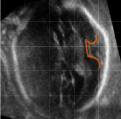

Cortical Plate Segmentation Using CNNs in 3D Fetal Ultrasound

Communications in Computer and Information Science

·

01 Jan 2020

·

doi:10.1007/978-3-030-52791-4_5